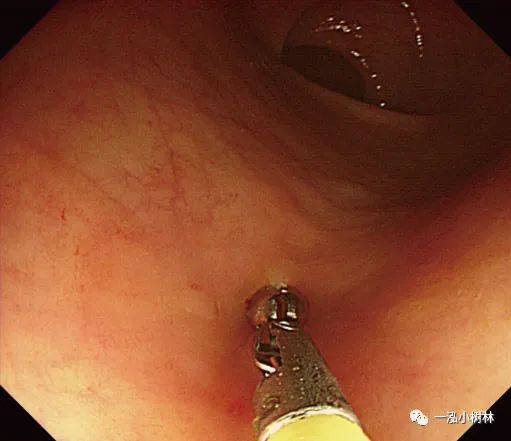

图5d 对病变进行机械性横切

图5e 对病变进行机械性横切